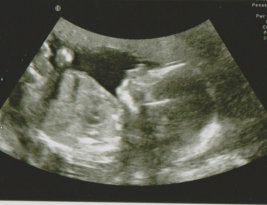

FÜRSORGE Schwangerschaftsfeststellung und Betreuung Nach Ausbleiben der Periode stellt sich die Frage, Schwanger?? Ab der 5. - 6. Schwangerschaftswoche lässt sich die Schwangerschaft mit Hilfe des Ultraschalls sicher nachweisen. Zweifel können durch eine Blutentnahme (HCG-Bestimmung - Schwangerschaftshormon) ausgeräumt werden. Die Schwangerschaft ist eine intensive Zeit für die werdenden Eltern. Wir begleiten Sie gerne. Untersuchungen Entsprechend der Mutterschaftsrichtlinien sind nach dem Ausbleiben der Menstruationsblutung regelmäßige Untersuchungstermine vorgesehen. Bis zur 30. Schwangerschaftswoche etwa alle 4 Wochen, danach alle 2 Wochen. Terminvereinbarungen für Schwangere sind kurzfristig möglich. Ultraschall Zur sicheren Diagnostik während einer Schwangerschaft gehört der Ultraschall (Sonographie). Dafür steht in unserer Praxis ein leistungsstarkes Gerät zur Verfügung. Das Gerät ermöglicht auch die Darstellung des Kindes 3/4-dimensional. Die Dopplersonographie erlaubt eine risikolose Messung des Blutflusses in den Gefäßen des Kindes und der Mutter. Dadurch können frühzeitig Hinweise für einen, sich vielleicht später entwickelnden Bluthochdruck oder eine Minderversorgung des Kindes, erkannt werden und entsprechend behandelt werden. Die hochempfindlichen Blutteste ab der 10. Schwangerschaftswoche können durch mütterliche Blutentnahme kindliche Chromosomenstörungen nachweisen. Die Erkennungsrate für eine Trisomie 21 (mongoloide Kinder) liegt bei 99%. Die Nackentransparenzmessung in der 11. Bis 14. Schwangerschaftswoche erlaubt (ohne Gefahr für das Kind) eine Risikobestimmung für chromosomale Störungen mit einer Sicherheit von bis zu 80%. In Kombination mit einer Laboranalyse steigt diese bis auf 90%. In der 15. oder 16. Schwangerschafts- woche gäbe es die Möglichkeit einer Fruchtwasseruntersuchung. Der Fehlbildungsultraschall wird in der 19. - 22. Schwangerschafts- woche durchgeführt. Hier werden alle Organe und Extremitäten dargestellt und auf Entwicklung und Funktion geprüft. Nicht alle, aber viele Fehlbildungen des Kindes können erkannt werden. Sonstige Untersuchungen Der Zuckerbelastungstest sollte in der 24. Schwangerschaftswoche durchgeführt werden. Der Schwangerschaftsdiabetes wird oft vernachlässigt, stellt aber eine große Gefahr für das Wachstum und die Entwicklung des Kindes dar. Dieser sollte frühzeitig erkannt und eingestellt werden, um Gefahren im Mutterleib zu vermeiden (Entwicklungs- und Anpassungsstörungen) und im späteren Leben des Kindes (Übergewicht und Bluthochdruck mit den dazugehörigen Folgeerkrankungen). Weitere diagnostische Möglichkeiten: Kardiotokogramm (CTG) Diese Untersuchung dient der Erkennung vorzeitiger Wehen und der Überwachung der kindlichen Herzaktion. Toxoplasmosescreening Eine Erstinfektion mit Toxoplasmose kann in der Schwangerschaft zu schweren Entwicklungsstörungen des Kindes führen. Ein Bluttest mit Bestimmung der Antikörper klärt, ob Schutz vorhanden ist, oder Überwachung bzw. Behandlung erforderlich ist. Streptokokkentest Streptokokken der Gruppe B kommen bei etwa 10% der Schwangeren in der Scheide vor, was während der Schwangerschaft kein Risiko darstellt. Bei der Geburt können diese Bakterien jedoch auf das Kind übertragen werden und ernste Infektionen verursachen. Ein Scheidenabstrich einige Wochen vor der Geburt zeigt, ob der Keim vorhanden ist. In diesem Fall wird während der Geburt eine schützende Antibiotika Behandlung durchgeführt. PH-Messungen des Scheidensekretes Im Rahmen der Vorsorgeuntersuchungen wird in der Praxis der pH-Wert gemessen, um Infektionen der Scheide zu erkennen und frühzeitig zu behandeln. Scheideninfektionen während der Schwangerschaft sind der Hauptgrund für Frühgeburten und einen vorzeitigen Blasensprung. Sie selbst können dies durch wöchentliche Selbstmessungen des Scheiden-PH-Wertes mit Messstreifen ergänzen. Im letzten Drittel der Schwangerschaft organisieren wir für Sie, auf Wunsch, eine Vorstellung in der von Ihnen gewählten Entbindungsklinik. Untersuchung nach der Geburt 6 bis 8 Wochen nach einer Geburt sollte eine Nachuntersuchung erfolgen. Diese Untersuchung beinhaltet: - Beurteilung der Rückbildung der Gebärmutter - Zytologische Untersuchung (Krebsvorsorge) - Untersuchung der Brust - Labor (Hb-Wert, Urin) - Beratung zur Empfängnisverhütung